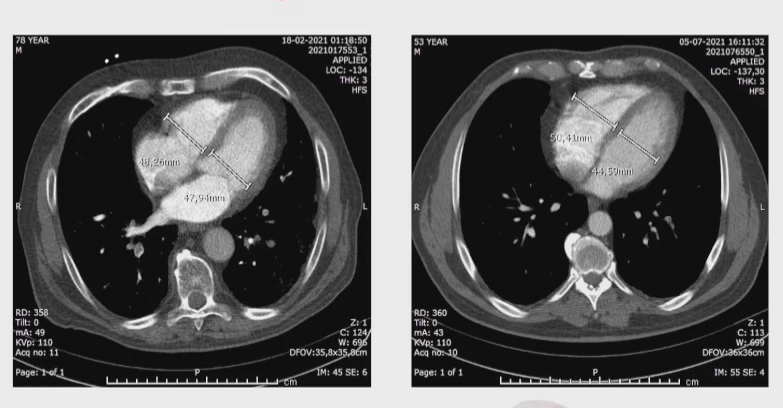

More anatomical changes seen on angio-CT in COVID patients